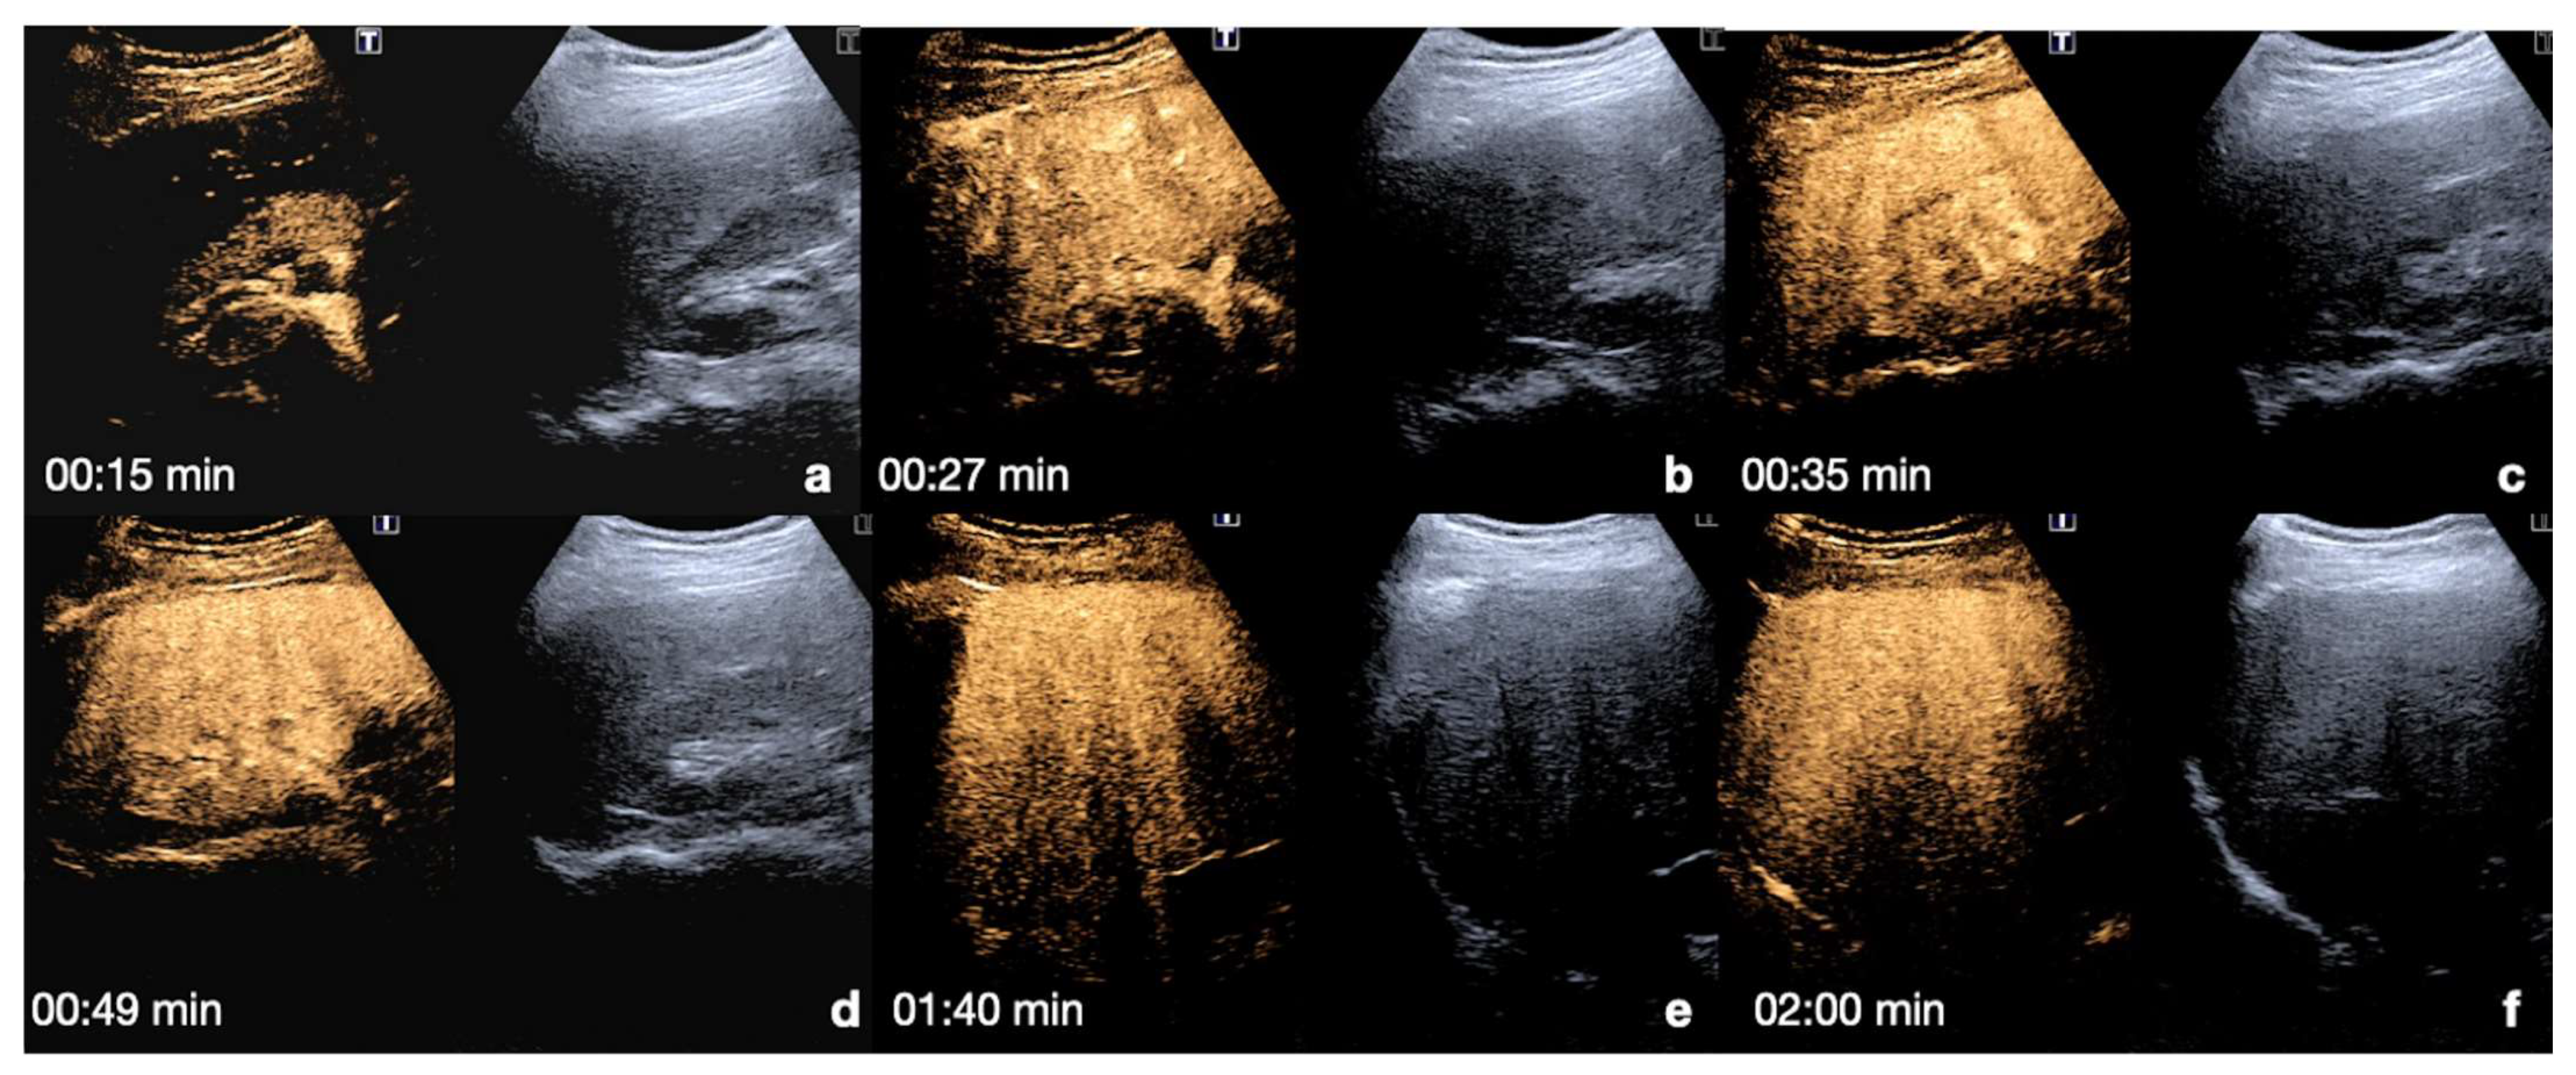

4. Case Series: Step-by-Step Practical Applications, Tips and Tricks during CEUS Follow-Up of Conservatively Managed Abdominal Trauma

4.1. Step 1

4.2. Step 2

4.3. Step 3

4.4. Step 4

4.5. Step 5

| 2–6 min | Venous-late phases: distribution of the contrast in the whole organ. Best time to depict parenchymal injuries. |

| Flash mode | Destruction of bubbles and possibility to re-evaluate an area of interest. |